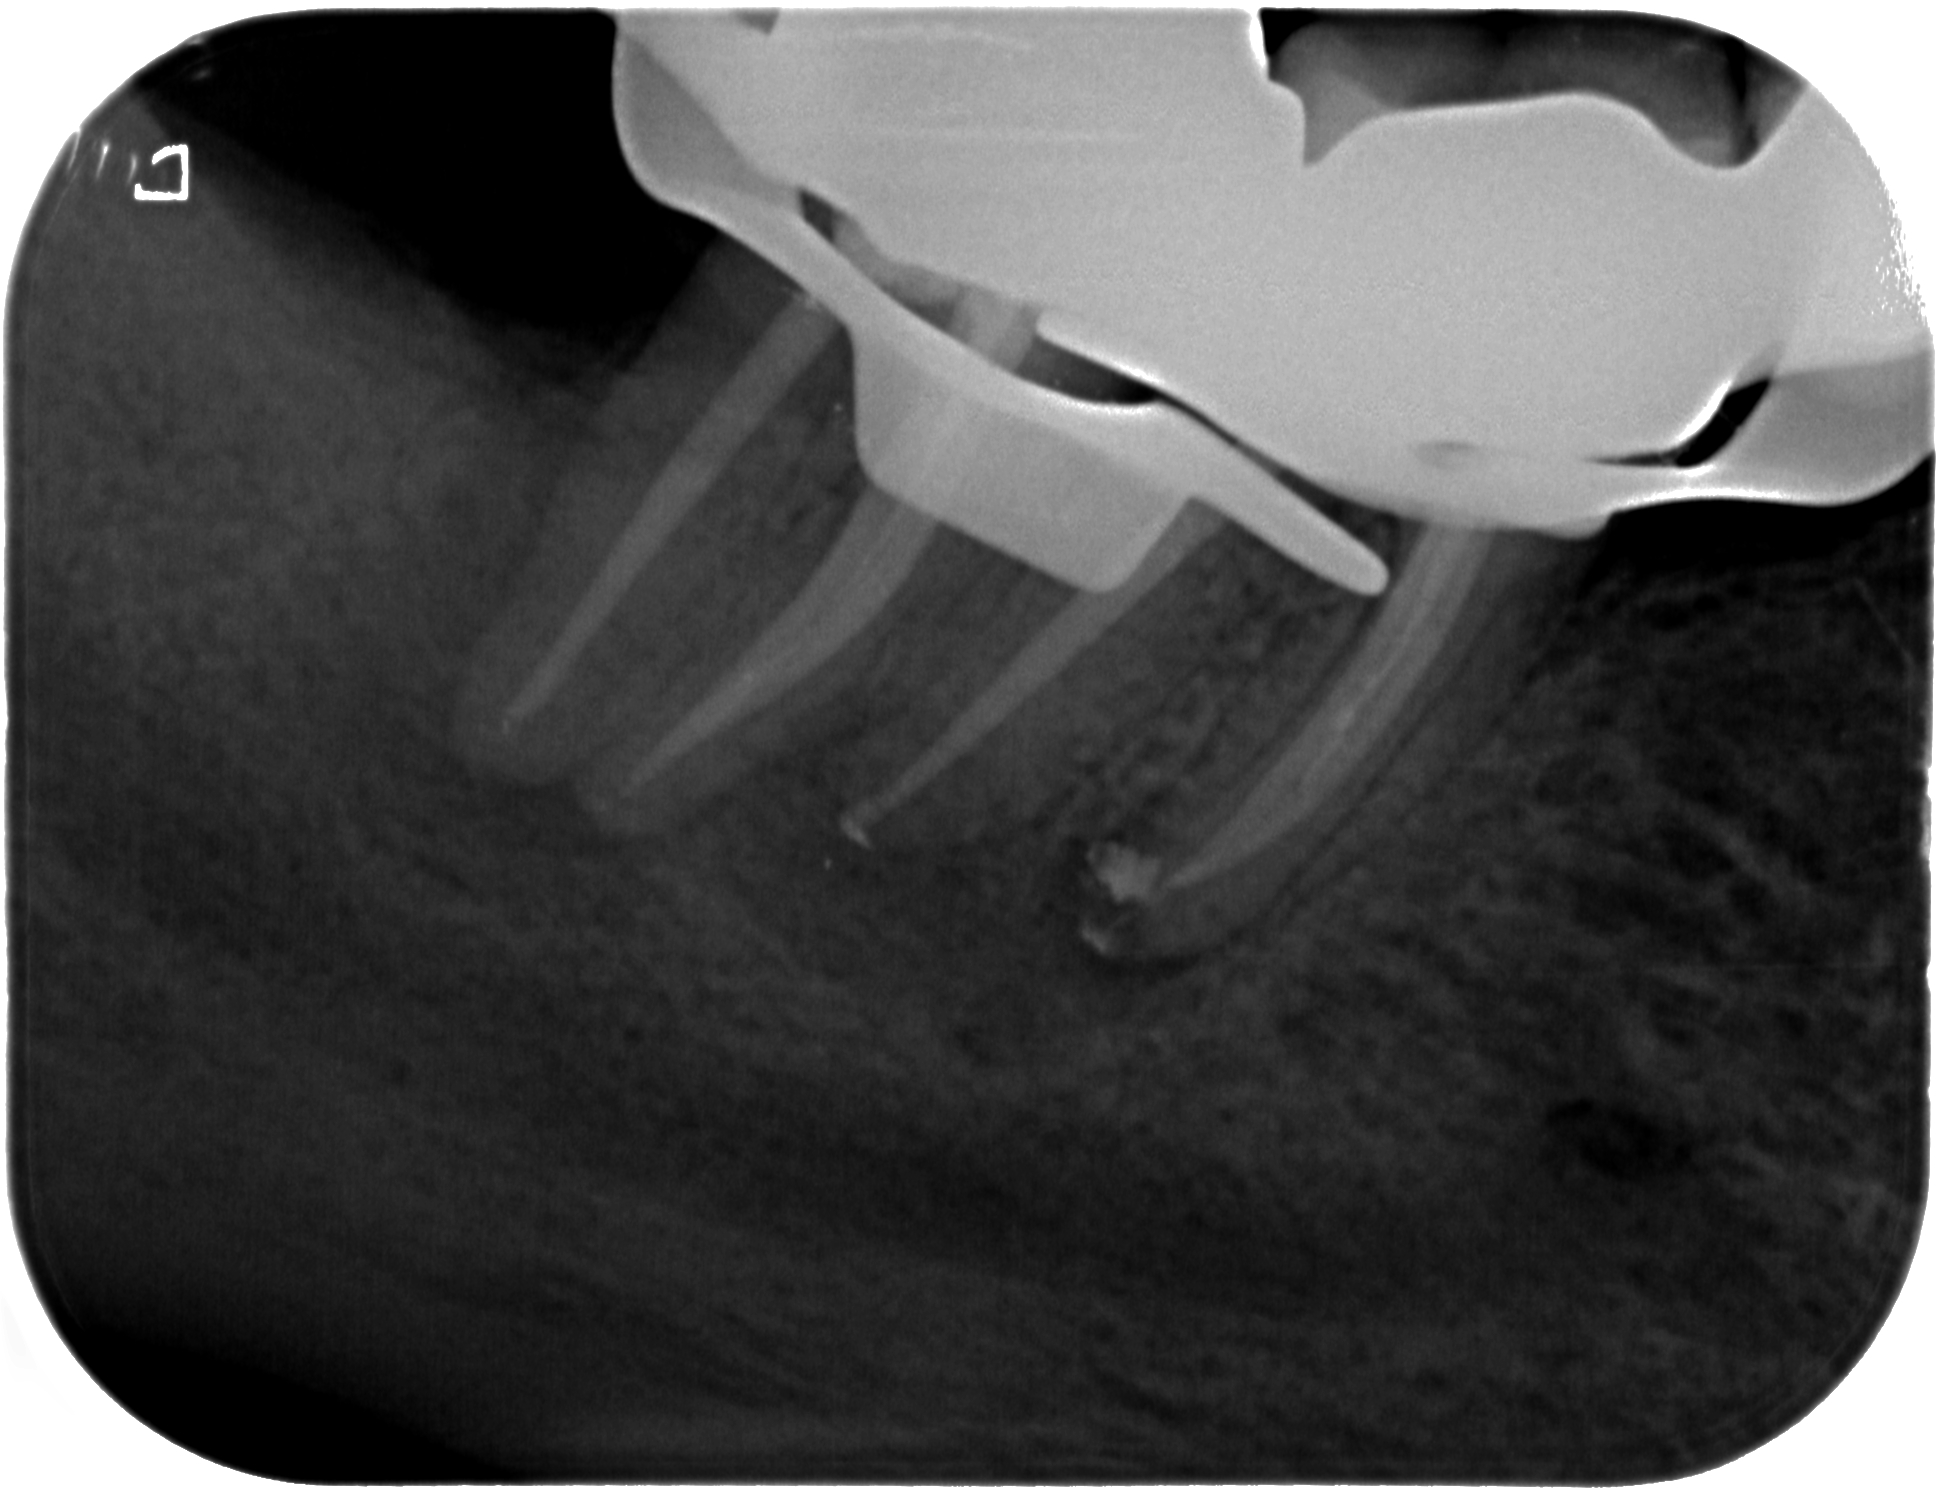

Pankatz-Rosemarie-19511101-X-20121010-113642-XHCSDQH3PELJ-3 Veröffentlicht 8. April 2013 am 1938 × 1489 in Was zeigt das DVT (2) – Die Auflösung